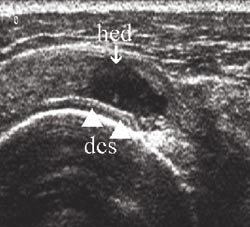

De tre tilleggskriteriene er den markerte fremstillingen av brusklaget i bunnen av cuffdefekten (double cortex sign) (fig 7), overflateforandringer på tuberculum majus (fig 8b) og væskeansamling i leddet og/eller bursa (fig 10a, b). Forandringene på tuberculum majus er følge av en mikrotraumatisering mellom den nakne beinoverflaten og acromion. Væskeansamling i leddet er best synlig i seneskjeden rundt det lange bicepshodet som hypoekkoisk halo, eller ved utposning av bakre leddkapsel (2, 6). Hollister og medarbeidere (7) fant en positiv prediktiv verdi for rotatorcuffruptur på 60 % ved væske i leddet, 70 % ved væske i bursa og 95 % ved væske begge steder, verifisert ved operasjon.

Figurene 2b, 3b, 4c, 5b, 6b, 8a og b er tatt med et Siemens Sonoline Antares ultralydapparat med 11,4 MHz lydhode, figurene 2b og 5b i tillegg med teknikk for utvidet bildefelt (extended field of view). Resten av ultralydbildene er tatt med et Siemens Sonoline Sienna ultralydapparat med 7,5 MHz lydhode. Figurene 1a, 1b, 2a, 3a, 4b, 5a og 6a er gjengitt med tillatelse fra Primal Pictures Ltd (). e-fig 3, e-fig 6, e-fig 11, e-fig 12 og e-fig 13 finnes i artikkelen på www.tidsskriftet.no